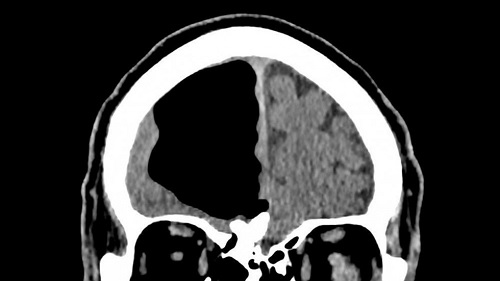

Bệnh nhân 84 tuổi có túi khí lớn ở não. Ảnh: SCMP |

Nói cách khác, các bác sĩ cho rằng không có lý do thực sự gây nên các triệu chứng của bệnh nhân. Chỉ sau khi chụp CT và quét MRI, đội ngũ y tế tại bệnh viện phát hiện sự thật kinh hoàng: Ở khu vực mà thùy não phải nên tồn tại thì bệnh nhân này lại chỉ có một không gian trống cực lớn.

Theo thông tin được đăng trên BMJ Case Reports, túi khí trong não của bệnh nhân rộng khoảng 8,9cm. "Trong khi nghiên cứu để viết báo cáo về trường hợp này, tôi không thể tìm thấy nhiều trường hợp trong những tài liệu có tính chất tương tự", bác sĩ Brown nói.